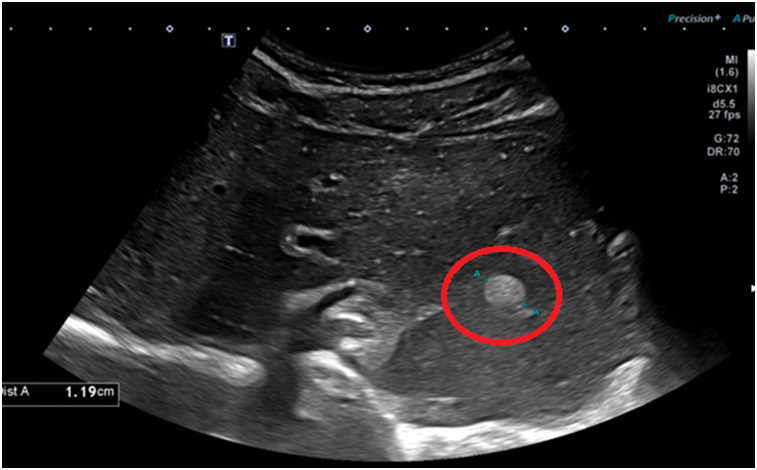

복부초음파 결과 왼쪽 간엽에 결절이 발견되었고, 정확한 진단을 위해 복부CT를 진행하였습니다.

1. 복부초음파

왼쪽 간엽 1.2cm 결절 — CT 동맥기 증강·지연기 소실 → 간선종 vs 간암 의심, 상급병원 정밀검사 전원.

• 복부초음파: 1.2cm 고에코 결절 복부초음파: 1.2cm 고에코 결절